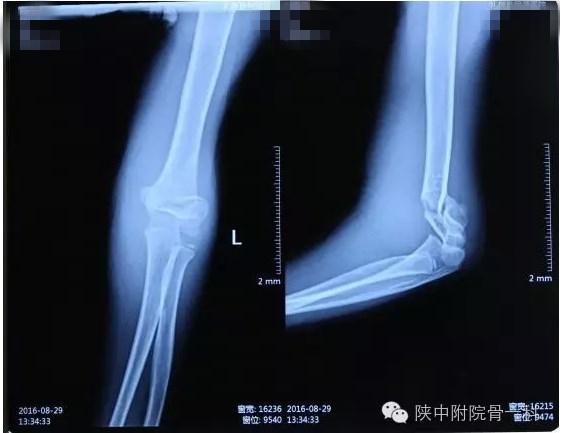

肱骨髁上骨折闭合复位手术记录,小儿肱骨髁上骨折手术恢复的概率 病案一:患儿XX,女,8岁,摔伤后左肘关节疼痛伴活动受限3小时入院。

肱骨髁上骨折闭合复位手术记录,小儿肱骨髁上骨折手术恢复的概率 诊断:Gartland Ⅱ型骨折